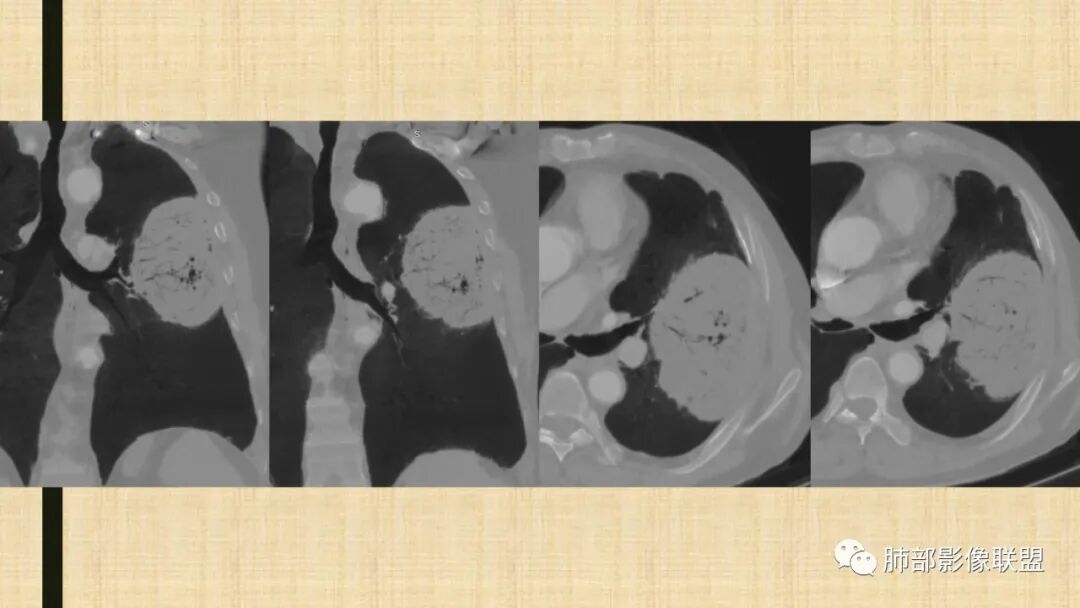

我再建一下血管。支气管进入,但是近端推移,堵塞

大肿块,边缘光滑,深分叶

近端支气管堵塞、推移为主

部分类似于脐凹征

内部支气管扩张

肺动脉推移为主,边缘部分进入

大肿块、表面光滑但深分叶,肺门侧支气管堵塞

回头看,内部支气管近端其实不连续,伴随肺动脉不存在

这两点就不符合